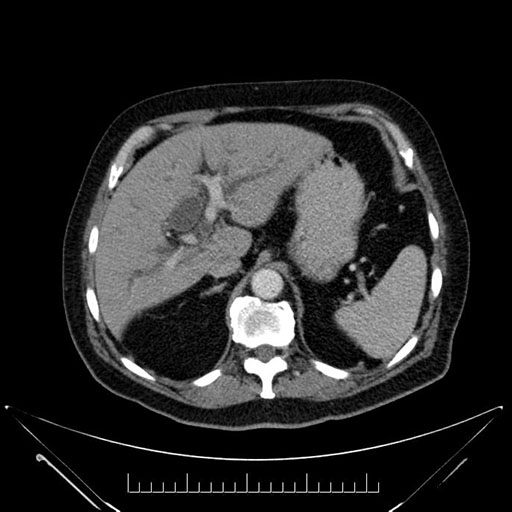

Axial - 3 months prior